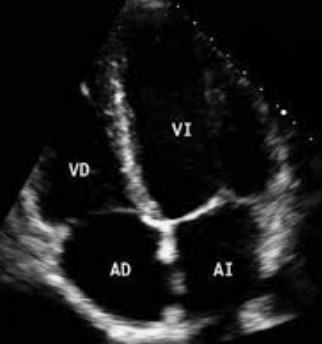

After defending my PhD at the University Complutense of Madrid (Spain) in cardiac electrophysiology, I did a first postdoctoral fellowship at New York University (U.S.) studying the physiology of cardiomyocytes in the context of arrhythmogenic right ventricular cardiomyopathy. I then joined the GENOXPHOS group to study the role of the tyrosine kinase Fgr in the heart.

Previous studies in our laboratory have shown that Fgr, in the mitochondria, upon stress, phosphorylates complex II of the electron transport chain. This leads to a change in the metabolism of the cell, which ultimately leads to inflammation.

My project studies the cardioprotective effect of Fgr inhibition to reduce cardiac inflammation. Our results could then serve as a foundation to explore treatment of other cardiac conditions in which an inflammatory component plays an important role such as myocardial infarction, atherosclerosis or arrhythmogenic right ventricular cardiomyopathy.